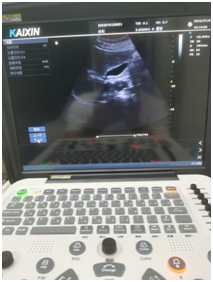

腹部B超和阴超(经阴道超声)都属于B超检查的范畴,在妇产科及腹部脏器检查中应用广泛,以下从多个方面为你介绍两者的情况: 一、检查方式 腹部B超:是将B超探头放在下腹部观察盆腔内情况,是一种非侵入性的检查方式。检查前需要患者适量憋尿,使膀胱适度充盈,以推开肠道气体干扰,更清晰地显示盆腔脏器。 阴超:是将探头套上一次性无菌探头套(通常是避孕套),然后缓慢放入阴道内,进行近距离的观察。检查前需排空膀胱,操作相对直接,但属于侵入性检查。 二、 优势 腹部B超:检查范围较广泛,除了可以观察子宫、附件等盆腔脏器外,还能对腹部其他脏器,如肝脏、胆囊、胰腺、脾脏、肾脏等进行检查。适合所有有检查需求的人群,包括未婚女性。 阴超:图像更清晰、分辨率更高,能更清晰地显示子宫、卵巢及盆腔的细微结构和病变,尤其对于肥胖患者或盆腔深部器官的观察效果更好。而且无需憋尿,节省时间,患者更舒适。 三、局限性 腹部B超:由于检查时探头与盆腔脏器之间隔着腹壁、膀胱等多层组织,可能会受到腹壁脂肪厚度、肠道气体等因素的干扰,对于一些较小的病变或位置较深的结构显示不如阴超清晰。此外,憋尿过程可能会让患者感到不适,且等待膀胱充盈的时间较长。 阴超:检查范围相对局限,主要用于观察盆腔内的生殖器官,对腹部其他脏器无法检查。同时,它不适合未婚女性、阴道畸形、阴道炎症急性期以及月经期的女性。 四、适用情况 腹部B超:常用于初步筛查腹部脏器的病变,如肝囊肿、胆结石、肾积水等;也适用于孕期检查,尤其是孕早期和孕晚期,可观察胎儿的发育情况、胎盘位置等。对于未婚女性的妇科检查,腹部B超是首选的检查方法。 阴超:常用于监测卵泡发育、诊断早期宫外孕、子宫肌瘤、子宫内膜病变、卵巢囊肿等妇科疾病。在辅助生殖技术中,阴超也是监测卵泡和黄体功能的重要手段。 这两种检查都是超声检查在妇产科常用的方式。腹部B超需要憋尿,使膀胱适度充盈推开肠道,以更清晰观察盆腔内器官情况,适合未婚女性、月经期女性等。阴超B超则是将探头放入阴道内进行检查,无需憋尿,图像更清晰,但不适合未婚女性、阴道出血较多者等。 即刻关注凯信微信号xzkxele,就能查看更多关于B超机、彩超机、兽用B超、宠物彩超的详情。(只需在公众号里搜;凯信超声;或扫描下方的二维码就可以加关注!)如需咨询报价信息,可联系客服热线15050003098 400-928-6626.